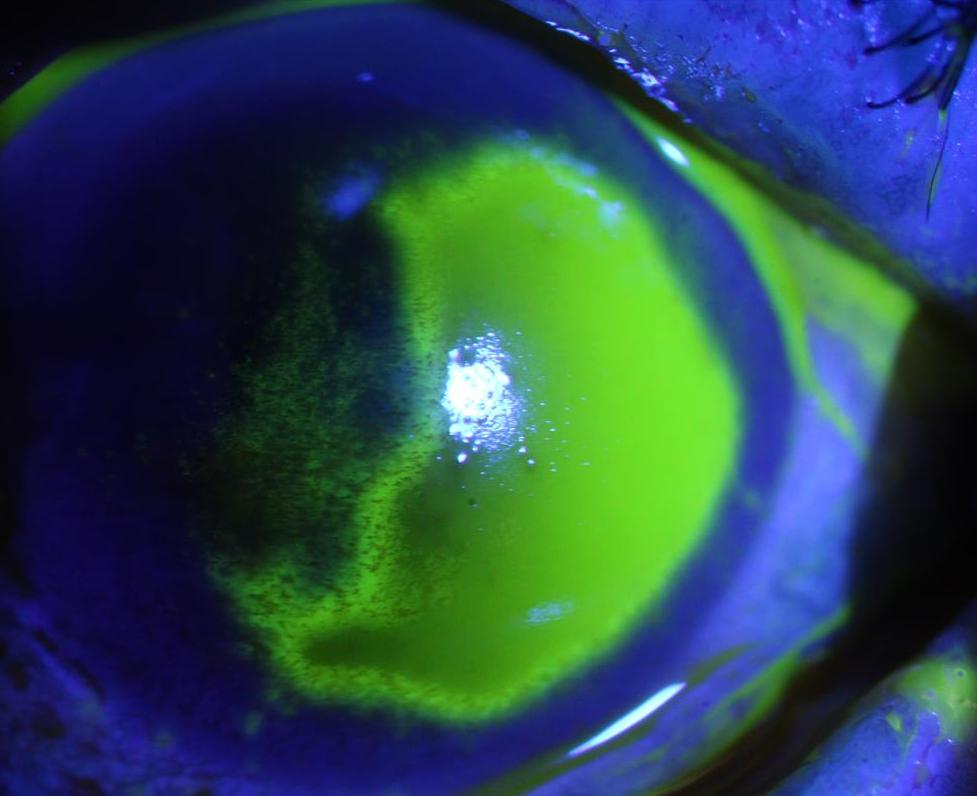

就诊前角膜荧光染色拍照检查

夏朝霞立即给王阿姨安排了角膜荧光染色拍照检查,发现王阿姨结膜已经充血,还出现了角膜损伤的情况,角膜上皮有大片剥脱。